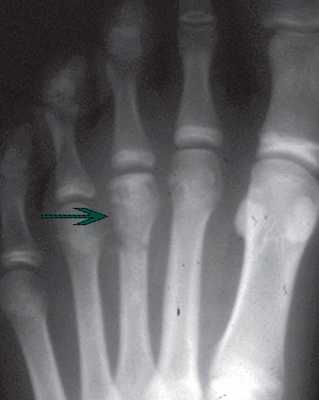

В IV стадию формируются переломы измененной субхондральной кости, приводя к появлению в полости сустава свободных тел.

На V стадии головка плюсневой кости значительно уплощена и расширена, суставная щели сужена, появляются грубые вторичные артрозные изменения.

Рентгенограмма на которой отмечается формирование крупного остеофита (стрелка) в области третьего плюснефалангового сустава.

Иногда единственной проблемой пациента является свободный фрагмент в полости сустава, и тогда бывает достаточно удалить только его, чтобы пациенту стало гораздо легче.

Выполняется маленький разрез над головкой плюсневой кости. Далее производится дебридмент (чистка) сустава, удаляются все свободные внутрисуставные тела.